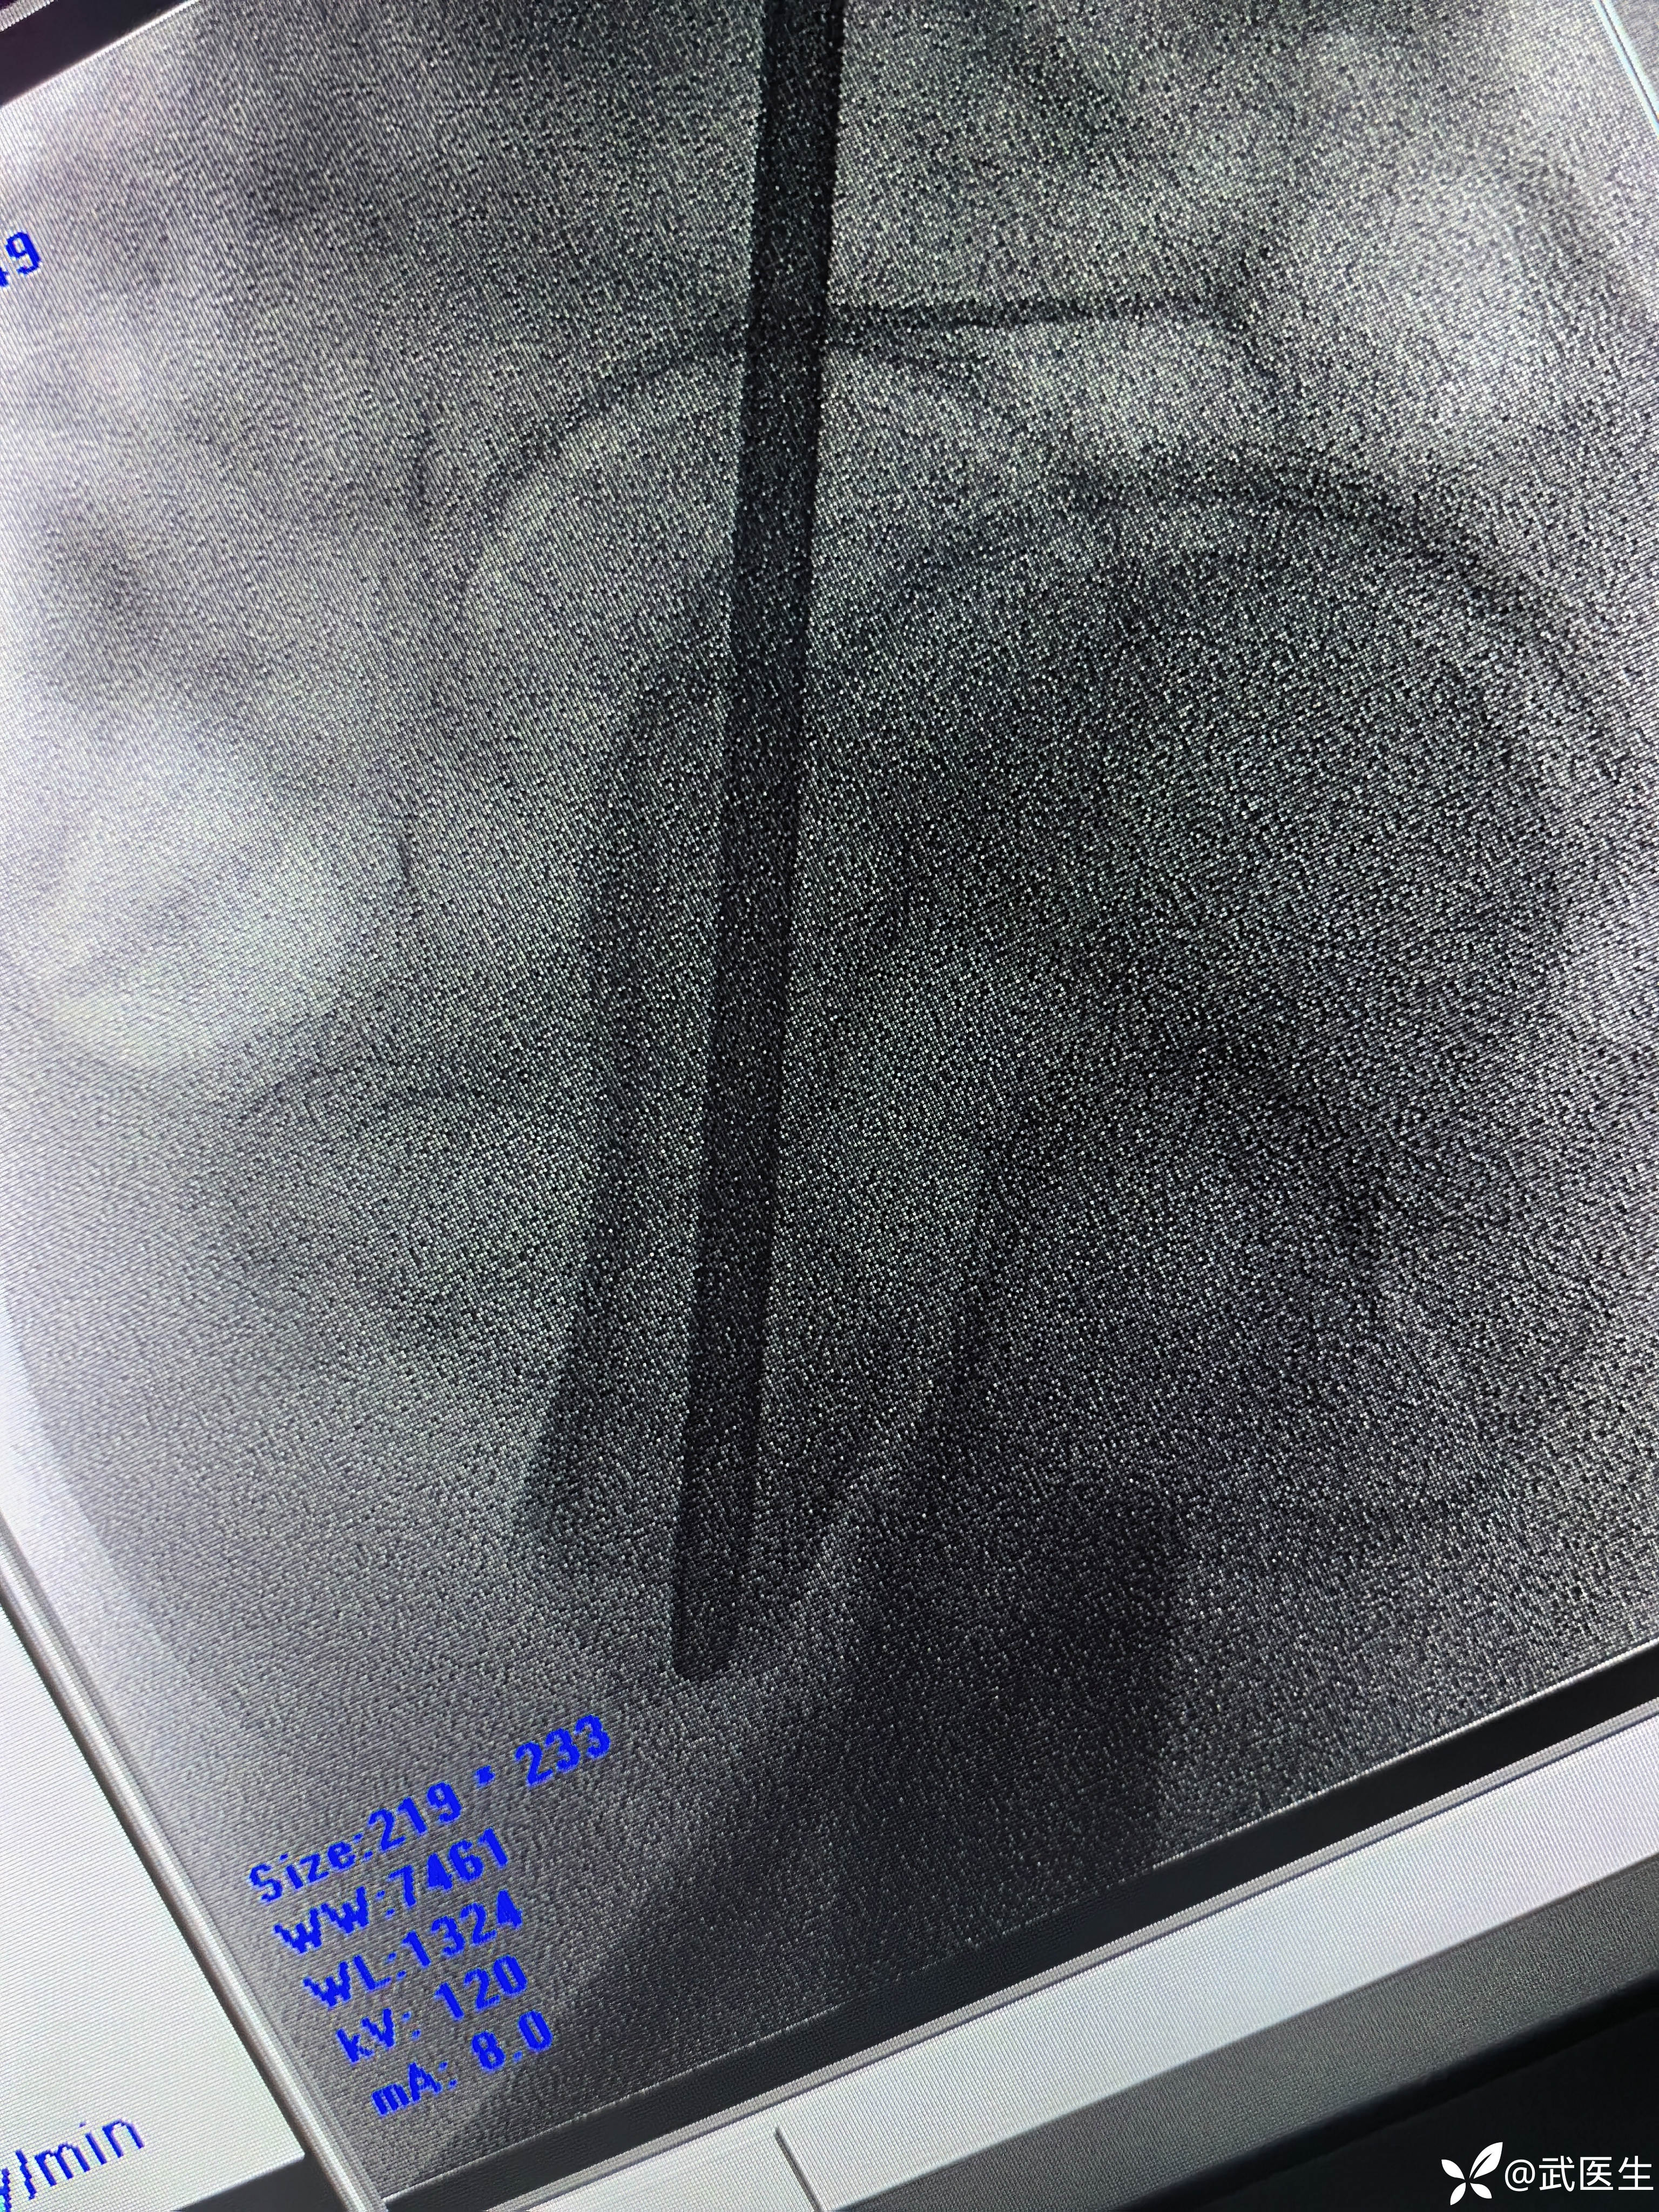

利用金手指置入导针,扩髓,步骤省略

置入合适髓内钉,如下

断端向外成角,对位不好,经常出现的问题,退出髓内钉,打阻挡克氏针,

置入